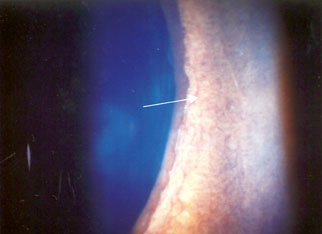

Figure 14: New vessels on the iris in PDR (arrowed)